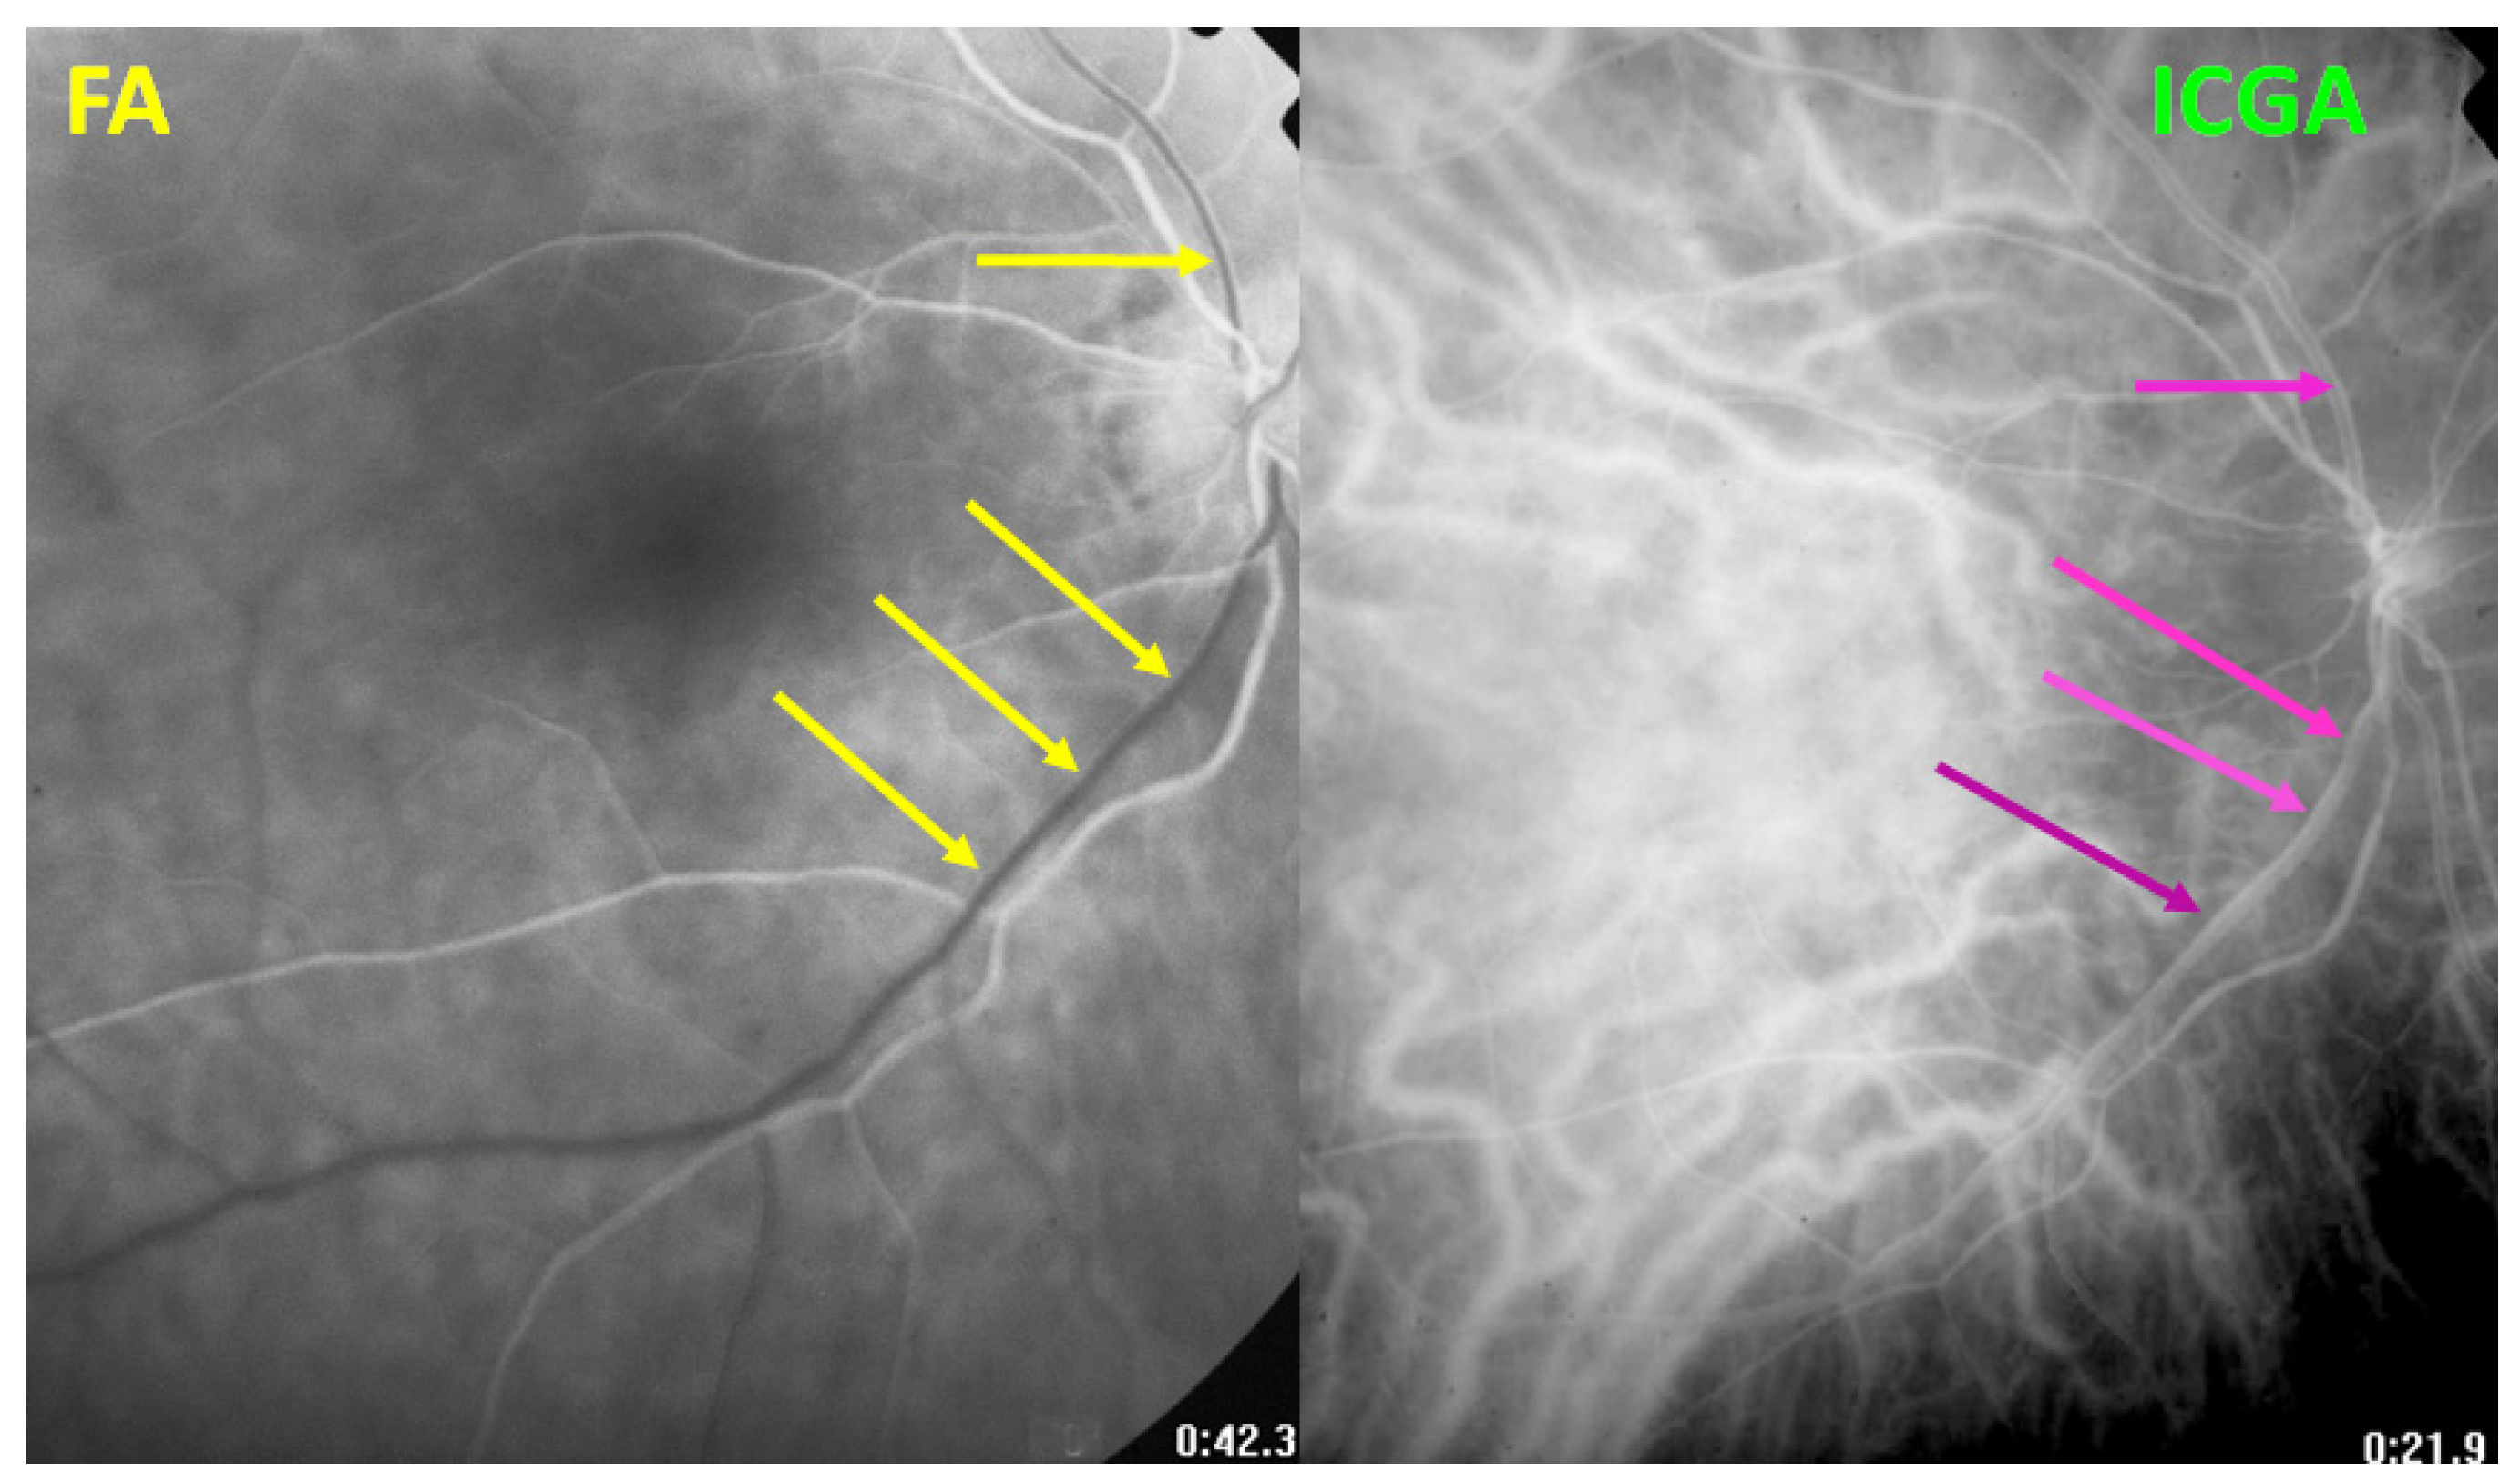

3.4.1. Fluorescein Angiography

3.4.3. Indocyanine Green Angiography (ICGA) Is Essential for Choroidal Involvement and Early Diagnosis

- Guex-Crosier, Y.; Herbort, C.P. Prolonged retinal arterio-venous circulation time by fluorescein but not by indocyanine green angiography in birdshot chorioretinopathy. Ocul. Immunol. Inflamm. 1997, 5, 203–206. [Google Scholar] [CrossRef] [PubMed]

- Tugal-Tutkun, I.; The Angiography Scoring for Uveitis Working Group (ASUWOG); Herbort, C.P.; Khairallah, M. Scoring of dual fluorescein and ICG inflammatory angiographic signs for the grading of posterior segment inflammation (dual fluorescein and ICG angiographic scoring system for uveitis). Int. Ophthalmol. 2010, 30, 539–552. [Google Scholar] [CrossRef] [PubMed]